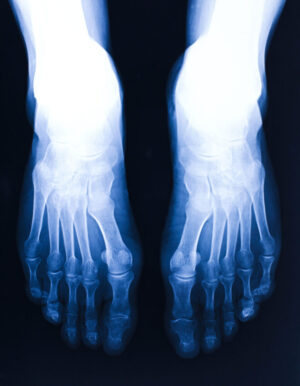

A bone density scan, as the name implies, is an imaging test that allows a physician to get a better understanding of the mineral density of a person’s bones. With the help of low-dose X-rays, a medical professional can assess how strong a person’s bones are to identify risk factors for different conditions, like osteoporosis.